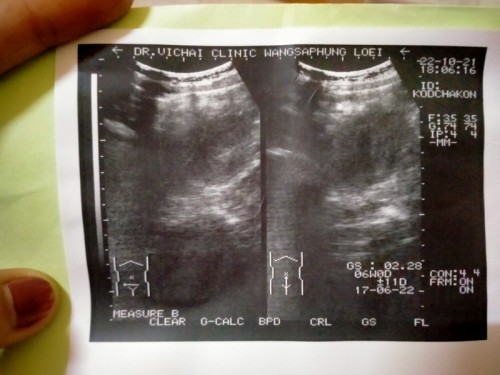

อยากรู้ว่าใช่ท้องลมใหม รึท้องปกติ😢ถ้าท้องปกติจะได้รีบบำรุง

บำรุงก่อนเลยค่ะแม่ ของบ้านนี้ ซาวด์ตอน7วีคไม่เจอตัวเด็ก 8วีค ไม่เจอ จน9วีคถึงจะเจอ

หมอได้แจ้งอะไรแม่หรือเปล่าคะ